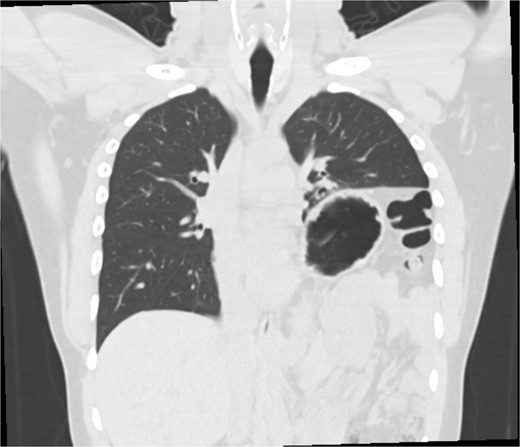

This is a case of a 26-year-old male patient who presented with symptoms of dyspnea on exertion, left chest pressure, and constipation for 7 years. He was a never smoker with no history of trauma, nor prior neck and chest surgeries. Baseline pulmonary functions tests revealed FEV1 of 71% predicted and DLCO of 77% predicted. Work-up included a computed tomography (CT) of the chest which revealed marked left hemidiaphragm elevation with compression atelectasis of the left lower lobe (Fig. 1). A fluoroscopic sniff test showed paradoxical movement of the left hemidiaphragm consistent with diaphragmatic paralysis. Interestingly, abdominal imaging obtained 14 months before surgery showed a displaced stomach but without volvulus (Fig. 2). Due to the impact on the patient’s quality of life, he was offered surgical treatment with a robotic-assisted left thoracoscopic plication of the diaphragm. This was done using a three-arm technique using the Da Vinci Xi surgical system (Intuitive Surgical, Sunnyvale, CA) with an additional assistant port. Plication was performed by placing multiple horizontal mattresses sutures reinforced with pledgets in an anterior–posterior orientation, and systematically working medial to lateral. A postoperative chest X-ray showed a satisfactory result (Fig. 3).

Pre-operative imaging revealing marked left diaphragm eventration.